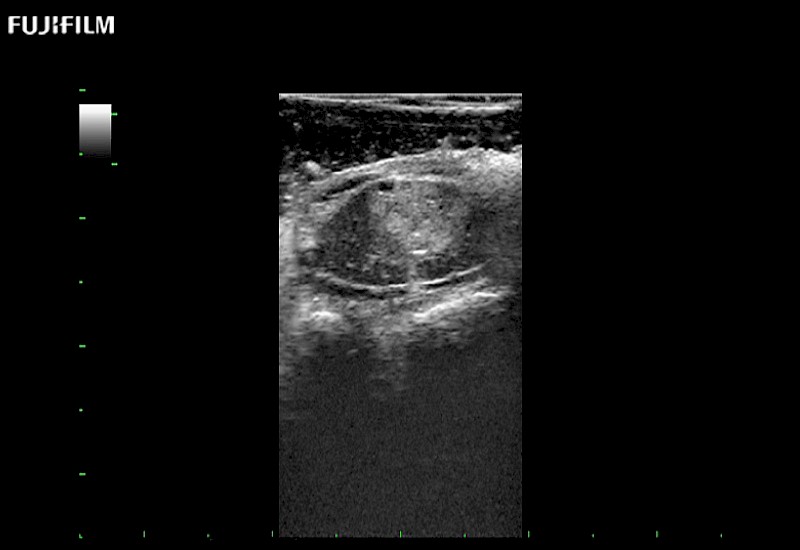

Tight curved (12mm) array transducer that is ideal for scanning during cranial guidance procedures.

Main Specifications:

Smaller footprint (20mm) curved array transducer that is ideal for scanning during cranial guidance procedures.